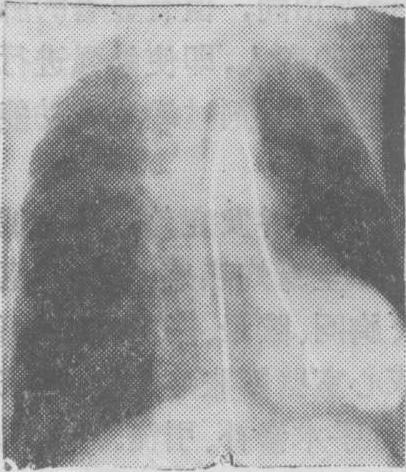

图1 瓣膜型肺动脉口狭窄选择性右心室造影侧位片

图示造影剂从右心室喷入肺动脉时呈细柱状影,肺总动脉呈明显的狭窄后扩张,状如动脉瘤。

(3) 右心室内: 在右心室流出道注射造影剂可显示漏斗部、肺动脉瓣和肺动脉狭窄(图1)。法乐四联症时在右心室注射造影剂可见主动脉及其分支无名动脉、颈动脉、锁骨下动脉和右心室流出道、肺动脉瓣、肺动脉一起显影,可见肺动脉瓣和漏斗部的狭窄情况(图2)。心室间隔缺损有右至左分流时,可见造影剂从右心室进入左心室; 在只有左至右分流的病人,如注射压力高,且造影剂在心室舒张期注入时,则造影剂亦可能通过心室间隔缺损而由右心室扩散入左心室。艾生曼格综合征 (心室间隔缺损型、动脉导管未闭型与主动脉肺动脉间隔缺损型)、大血管错位、右心室双出口、肺动静脉瘘和肺动脉扩张等亦可在选择性右心室造影过程中得到显示。